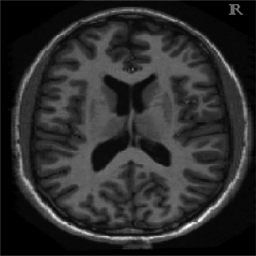

In Figure 1.1 the influence of the choice of a constant in (1.1) is shown, over-regularising the reconstructed image if chosen too small and under-regularising if chosen too large. Moreover, in Figure 1.2 the reconstructed images with constant and spatially-dependent are shown, where has been optimized with the bilevel approach for (1.1) proposed in [9].

4.1. Uniform Gaussian noise

In this first experiment, we consider the denoising problem with brain scan images. The first set consists of images of pixels and Gaussian noise with zero mean and variance . The original and noisy images are shown in Figure 4.1. The domain decomposition-semismooth Newton algorithms run with the parameter values , , and . The results are shown in Figure 4.2. From the surface representation of , we can observe that is continuous and its shape is related to the one of the original image. In particular, the regularization is stronger in homogeneous regions in the image, and weaker where the image intensity undergoes variations on a smaller scale.